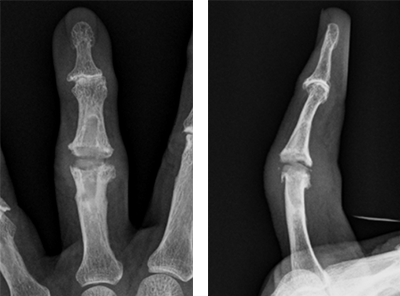

ブシャール結節に対しては、シリコンインプラントを用いた人工関節置換術を行います。PIP関節の動きを保ちながら、痛みの改善が期待されます。

ブシャール結節に対する人工関節置換術